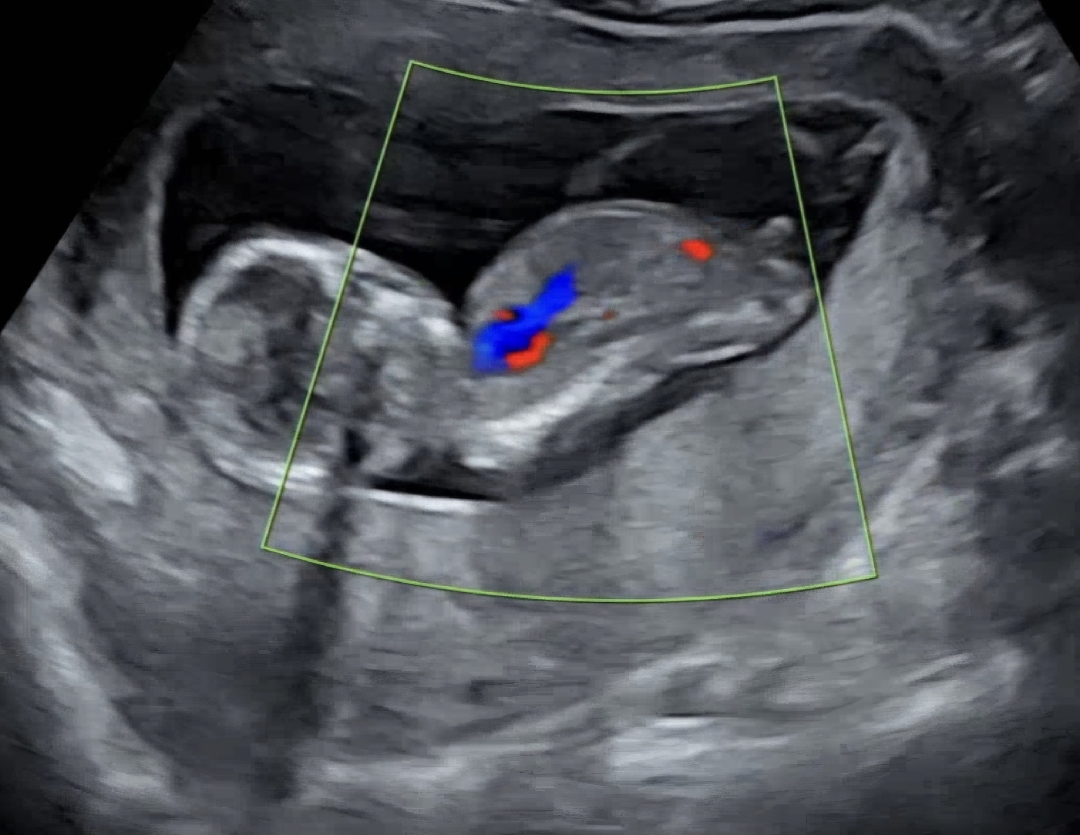

12주6일차, 각도법...궁금해요..!!

입체초음파 촬영할때 몸을 많이 움직였거든요..! 지금 사진도 몸을 조금씩 옆으로 비틀려고 할때 캡쳐한거라 각도법으로 봤을때...평행인건지 30도이상이라고 봐야하는건지 모르겠네요🥲 성별이...너무 궁금해요!!🙏🙏